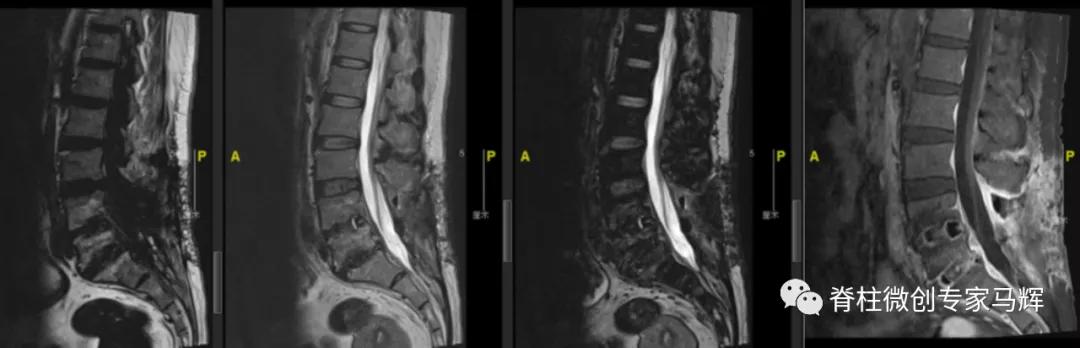

54岁的张女性,因为左髋部疼痛,行走不便2天,在当地医院就诊。查CT显示腰椎骨质增生,L2-3、L3-4椎间盘膨出。L4-5、L5-S1椎间盘术后改变,部分椎板缺如。L5-S1硬膜囊及右侧神经根受压而显示不清。入院后予以抗感染、活血等相关对症治疗,症状无明显缓解,当地医院建议转上级医院进一步诊治。为此,张女士一家慕名来到了上海第九人民医院脊柱外科就诊。

入院的时候,张女士有腰痛,左下肢疼痛无力伴发热6天,近3日疼痛加剧,翻身抬腿困难,发热最高达到38°C。根据症状,体格检查,实验室检查和影像检查,判断张女士可能存在脊髓硬膜外脓肿(SEA)压迫神经,以及感染的情况。为什么会出现这种状况呢?

最近这几年的手术经历让张女士的身体状况不是很好,可能存在免疫力存低下的情况。脊柱手术后可能存在医源性感染种植,进一步的腰椎间盘膨出,让张女士更容易出现脊髓硬膜外脓肿(SEA)感染的情况。SEA可通过血行播散或者通过邻近椎间盘炎或骨髓炎直接蔓延。

2018年腰椎术前

2018年腰椎术后

2019年腰椎内固定取出后